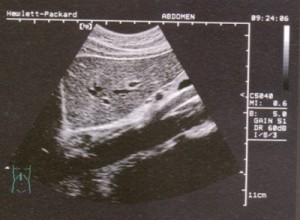

2.彩色B超示肝血管瘤樣改變。

3.CT檢查:肝內有密度均勻的低密度區,增強後腫瘤邊緣區可出現“C”形增強帶。